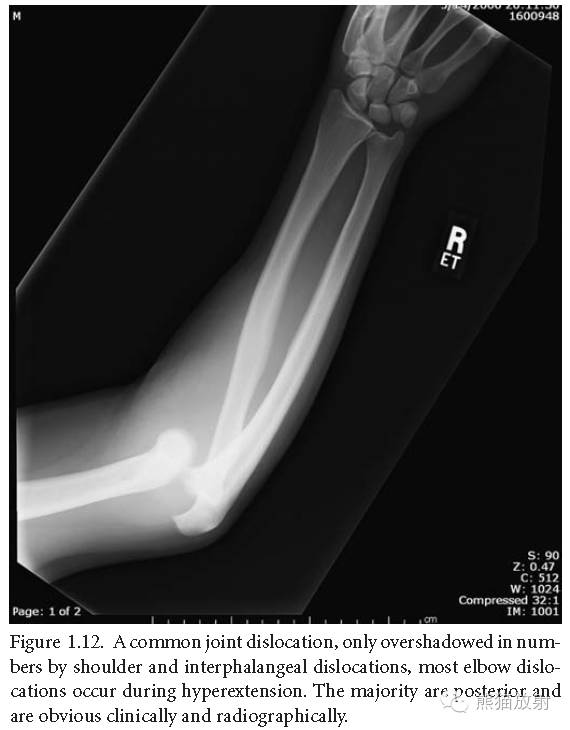

肘关节脱位:一种常见的关节脱位,仅次于肩关节及指间关节脱位。大部分肘关节脱位发生于过伸体位(当跌倒时手掌着地,肘关节完全伸展),后脱位最常见,尺骨鹰嘴向后移位,而肱骨下端向前移位。